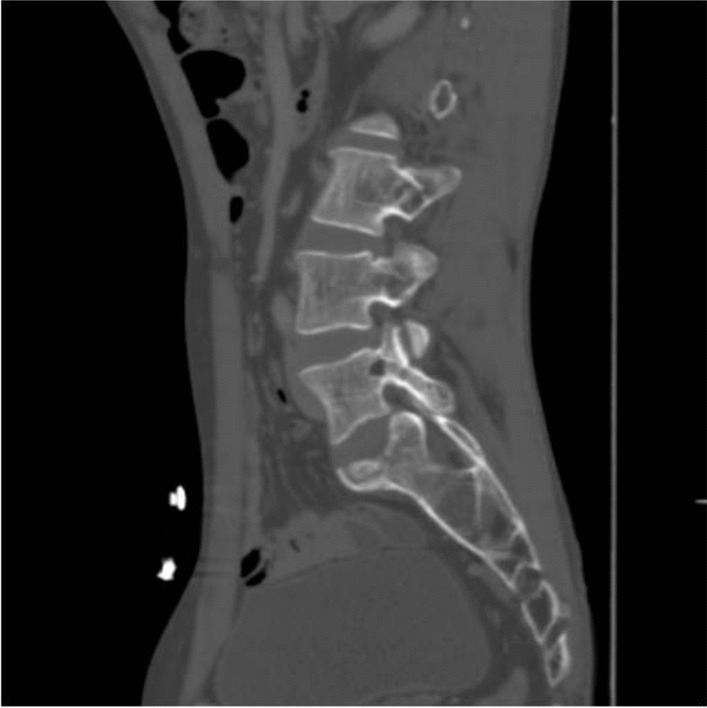

The bone algorithm of the lumbar spine in the sagittal section shows a focal lytic lesion in the left pedicle of the L5 vertebra suggestive of bony metastasis (Fig. 5).

Fig. 5.

The bone algorithm of the lumbar spine in the sagittal section shows a focal lytic lesion in the left pedicle of the L5 vertebra suggestive of bony metastasis